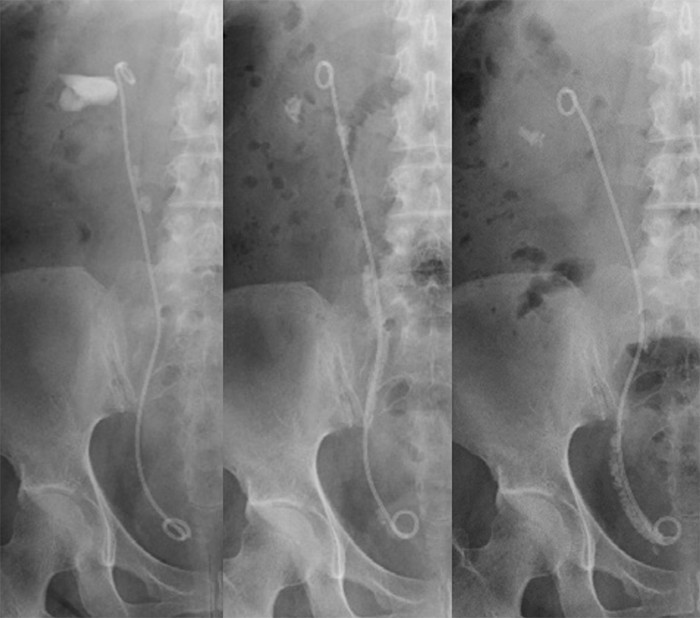

当院におけるECIRSのトラクト作成手順

- 膀胱鏡を用いてセーフティガイドワイヤーを挿入

- 半硬性尿管鏡で可及的頭側まで尿管を観察(+尿路造影)

- 尿管アクセスシース(UAS)を挿入(11/13F or 12/14F)

- 軟性尿管鏡で穿刺腎杯の観察

- US(eFLOWモード併用)にて穿刺腎杯決定

- 22G US穿刺針にて腎杯穿刺(軟性尿管鏡にて穿刺部位、動脈性出血の有無を確認)

- シリコンチューブからガイドワイヤーをUAS内に落とし込みthrough & throughとする。

- ダイレーターで12Fまで拡張し2本目のガイドワイヤー(セーフティガイドワイヤー)を留置。

- UAS内にあるthrough & throughのガイドワイヤーを用いてトラクトを作成する。

- 腎盂鏡は全例mini-Percを用い、Ho;YAGレーザーを使用しバスケット鉗子で抽石する。